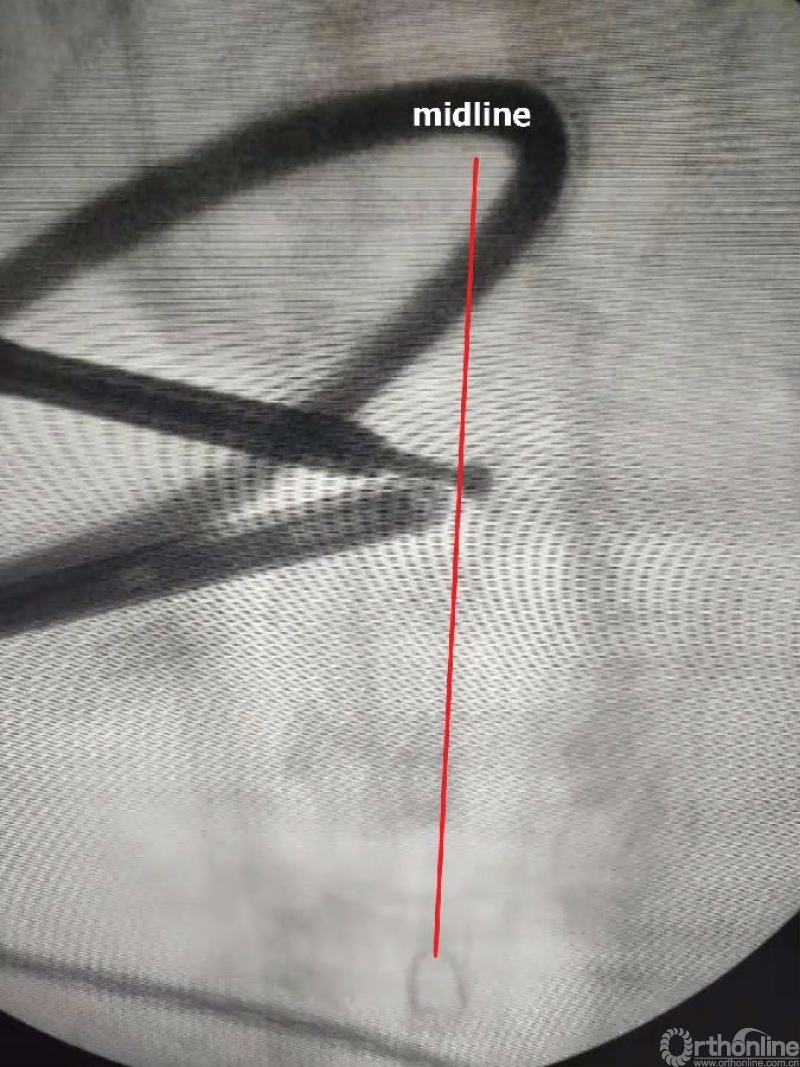

1. 术中如何确定中线?

临床上,0°镜子绝对是颈椎UBE的最好用的镜子,但是30°的镜子对侧中线结构的显露及对侧结构的显露具有更广角的视野。在进行同侧减压之前,中线结构的显露是关键。